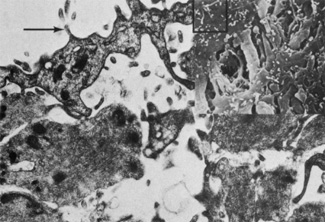

Several cell types have been described in the stroma of the iris. These include fibroblasts, melanocytes, mast cells, clump cells, macrophages, and lymphocytes. Fibroblasts are the most prominent cell type and are often found in close association with blood vessels, muscles, and nerves. The fibroblasts are concentrated toward the surface of the stroma and rest above many of the melanocytes. Their ultrastructure is similar to that described for fibroblasts of the anterior border layer. Melanocytes can be found around the adventitia of blood vessels, and they form plexuses with fibroblasts and adjacent melanocytes (Fig. 13). The character of melanosomes varies among irises of different colors and is similar to that described previously for anterior border melanocytes. An unusual type of macromelanosome has been identified in the cytoplasm of stromal melanocytes in patients with melanosis oculi. These abnormal melanosomes are not seen in the posterior pigment epithelium in these patients, suggesting that melanosis oculi is a disorder of neural-crest derived melanocytes.31

Fig. 13. Melanocytes (M) are oriented parallel to the iris surface (×10,500). Inset shows junctional complex (arrow) connecting melanocytes (×64,500).

Clump cells of Koganei are most commonly found just anterior to the pupillary sphincter muscle and in the anterior ciliary body near the iris root, although these cells can be seen elsewhere in the iris stroma. These cells can vary in size (up to 100 microns) and appear as heavily pigmented, round cells on light microscopic examination. It is now generally accepted that the term “clump cell” actually includes two distinct populations of cells distinguished by their microscopic features.7,32,33 Type I clump cells are the predominant cell type seen and are probably macrophages. Transmission electron microscopic examination reveals that the type I clump cells have delicate villi projecting from their surface and that their cytoplasm is densely filled with clusters of melanin granules of varying sizes and shapes (Fig. 14). The nucleus is often eccentrically located, and the cells typically contain round or irregular bodies that are thought to contain either lipid or lipofuscin. These cells have no basement membrane. Type I clump cells are difficult to find in the irides of children, and increase in number with patient age. Like macrophages, the proposed function of Type I clump cells is to ingest released melanin from pigment released from dying cells. Type II clump cells are less common and are thought to represent smooth muscle cells in arrested stages of development. Light microscopic examination shows that type II clump cells have a more regular outline with more homogenously distributed pigment granules than type I clump cells. Transmission electron microscopy examination shows that type II clump cells are a group of cells that contain pigment granules identical to those found in the iris pigment epithelium. These cells may form clusters surrounded by a continuous basement membrane and are bordered by apical villi that extended into cleftlike spaces. These cells are attached to each other by desmosomes and contain intracytoplasmic filaments and micropinocytic vesicles.33

Fig. 14. Type I clump cell (macrophage) in the pupillary region (×18,000).